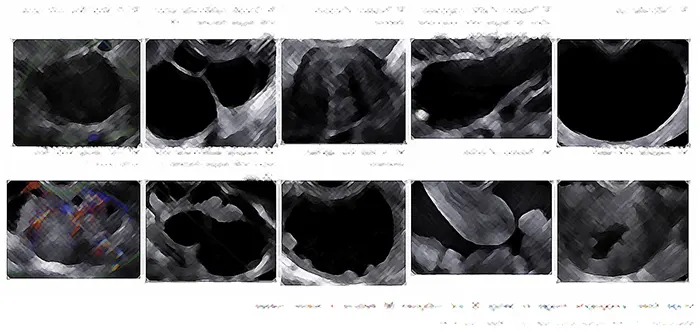

먼저 문진을 통해 통증, 부정출혈, 구토, 변비, 불임 등의 상태를 자세히 듣고, 자궁내막증이 의심되는 경우 내진을 통해 자궁, 난소 촉진 및 경질초음파 검사로 병변의 유무, 크기 등을 확인합니다.초콜릿 낭종은 초음파 검사로 비교적 쉽게 발견할 수 있지만, 낭종 내에 덩어리 같은 것이 있는 등 악성 종양의 가능성이 있는 경우에는 MRI나 CT, 종양표지자 등의 검사를 시행합니다.